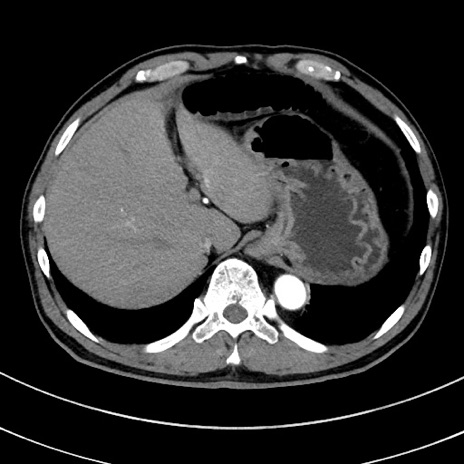

症例8(横断像)

【症例】 60歳代男性

【主訴】 黒色吐物

【現病歴】 4日前から嘔気自覚、2日前の朝食後にも嘔気あり、自分で手で嘔吐反射起こし嘔吐したところ血が混ざっていたため受診。

【既往歴】 5年前汎発性腹膜炎を伴う急性虫垂炎で手術、高血圧、前立腺肥大症、高脂血症

【身体所見】 腹部正中に手術癩痕あり 腹部平坦・軟圧痛なし膨満感あり

【データ】WBC 8400、CRP 4.54